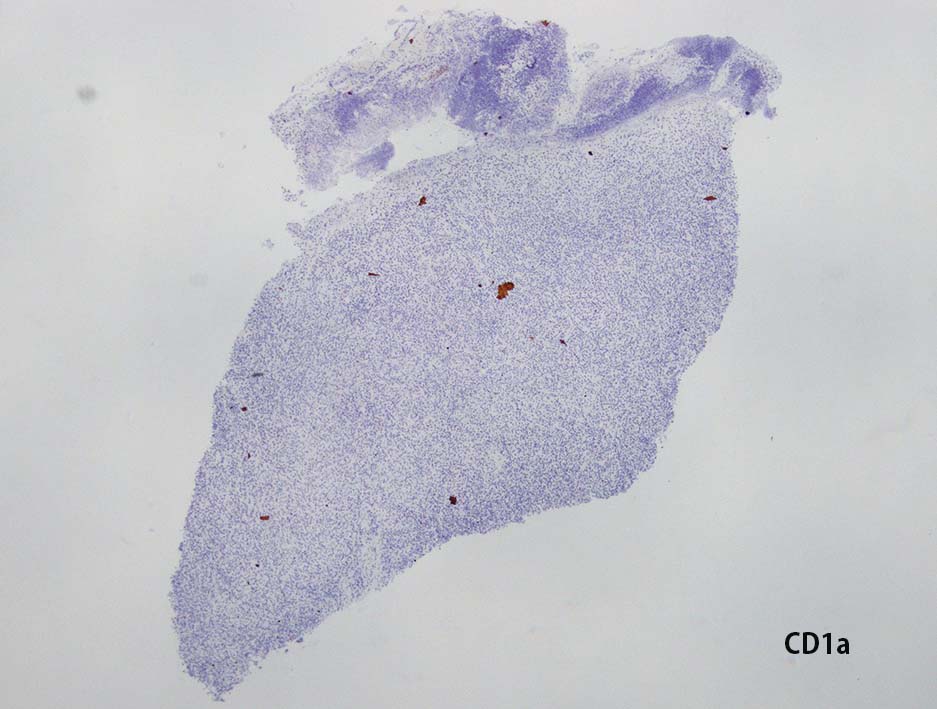

CD20, PAX5, CD3, CD5 リンパ球マーカは陰性. Dendritic cell marker (CD1a, CD123, Langerin, etc)は陰性. S-100, CD168, CD68(KP-1)が陽性. 組織球増殖病変と考えられた. foamy macrophageやgiant cellsはほとんど認められない. 高異型度, 多型細胞の出現はないが, MIB-1 LIが高く, mitosisも増加している, 悪性の心配あり, 治療方針の決定のため consultationを行った.

IHCの拡大像. Factor XⅢaの免疫染色画像もここに掲載する.

典型的なJXG細胞は大きく, 細胞質は空胞状で,核は円形または切れ込みをもち, 小さい。細胞は、CD68、fascin、factor XIIIa、CD4で染色されるが、CD1aやCD207では染色されない。*2